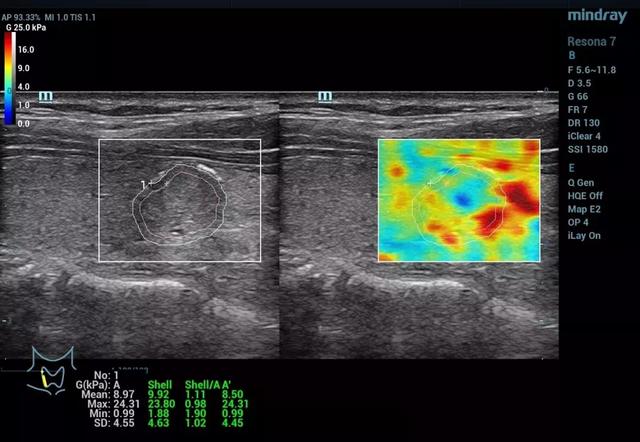

大会期间,深圳人民医院超声科董发进博士分享了基于迈瑞Resona 7的多模态弹性成像技术关于甲状腺癌诊断的最新研究报告。迈瑞的剪切波弹性成像提供了应变弹性和剪切波弹性成像的多模态弹性技术进行组织硬度的测量,其弹性比(Elastic Ratio, EI)和剪切模量(shear module, G)可以用于进行定量分析。研究报告的目的是应用全新可量化的剪切波弹性比和剪切模量进行甲状腺恶性结节的评估。

研究结果显示,恶性甲状腺结节的平均弹性比明显低于良性结节。(P<0.001)敏感度和特异性分别达到71%和73%。恶性甲状腺结节的剪切模量最大值,平均值和标准差明显高于良性结节。(P<0.005)。在剪切模量最大值的参考值(cut-off value)设置在15.82kPa的条件,能获得最高的AUROC值(0.84),敏感度和特异性分别达到79.17%和79.03%。研究结果表明,可量化的剪切波弹性技术将会是一个新的辅助诊断甲状腺结节良恶性的超声工具之一。

甲状腺乳头状癌病例(1)